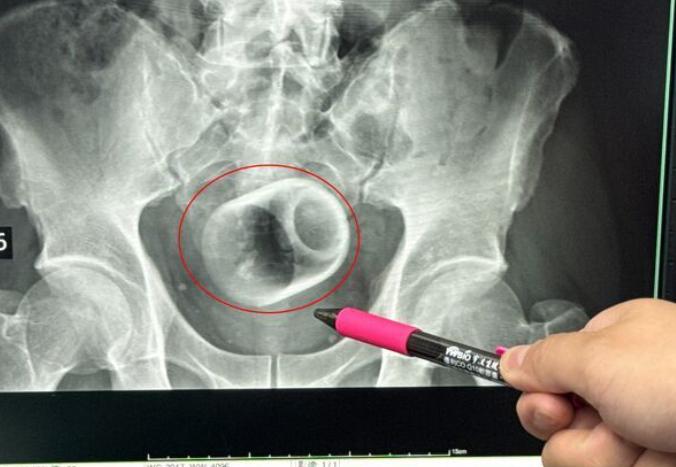

对岸奇葩天天有! 台媒:台湾省中部一名男子腹胀三天无法大便,肚子痛到受不了,赶紧到医院求诊,医师透过X光检查,惊见患者的肛门竟然塞一个直径约6公分、高约8公分的陶瓷杯,原本要用器械夹出杯子,但杯缘光滑无法施力,杯子全被大肠包住,部分肠子缺血也造成坏死,最后全身麻醉“开肠破肚”的才顺利取出杯子。